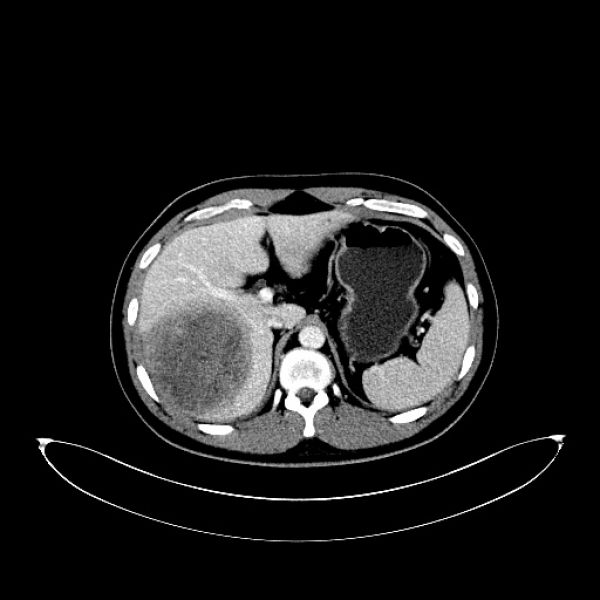

患者入院后肝胆外二科积极诊治,肝胆脾增强CT示:肝右叶占位,性质待定:考虑原发性肝CA(巨块型)并子灶形成,其他待排,AFP〉1210.0ng/ml,乙肝病毒PCR,9.78E+0.4IU/ml。结合病史及相关检查结果,术前诊断:1.右肝占位:原发性肝癌可能性大?2.乙肝。术前请感染科会诊加用恩替卡韦分散片抗病毒治疗。告知患者及家属原发性肝癌可能性大的事实,作为家庭主要劳动力的患者,在病魔面前没有妥协,毅然决定积极配合治疗。面对患者的信任,肝胆外二科治疗团队不敢丝毫懈怠,科主任姚本能主任医师与副主任杨定华副主任医师仔细阅片,经讨论后为患者完善肝脏3D成像,通过3D显像技术,精确了解瘤体位置和瘤体与动、静脉关系。术前精准评估,明确肝肿瘤主要位于肝S7、少部分位于肝S5、S8。因瘤体巨大,位置深,合并乙肝肝硬化,术中显露困难,手术难度极大。又组织全科室医师术前讨论,为了减少术中对肿瘤的挤压,拟定了行胸腹联合切口实施手术的方式,实现肝癌根治性切除,使患者最大程度获益。

术前CT图片